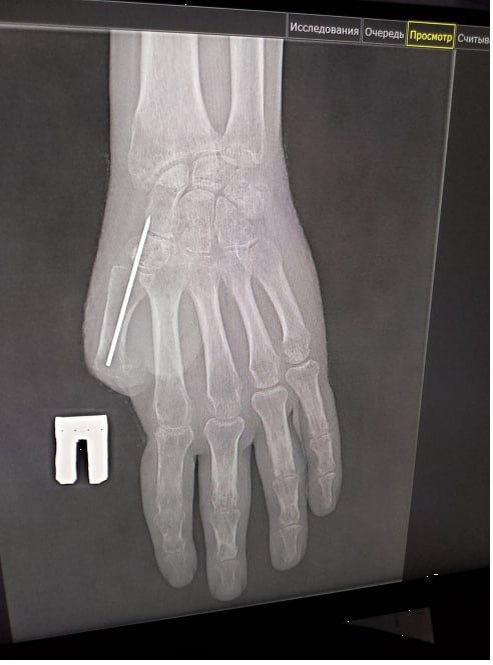

В Прокопьевске врачи восстановили палец руки участнику СВО, который пострадал от взрыва.

Первую операцию провели в начале этого года. Заведующий микрохирургическим отделением Прокопьевского ортопедо-хирургического центра Андрей Сигарев убрал грубые рубцы и виртуозно сформировал основу для будущего большого пальца.

В ходе следующей операции специалисты сформировали первый луч кисти и выполнили пластику «китайским лоскутом» – пересадили на кисть лоскут ткани с собственными сосудами. Такая методика гарантирует полноценное кровоснабжение и надежное приживление.

В ближайшее время проведут коррекцию прижившегося лоскута и углубление межпальцевого промежутка, чтобы придать кисти еще больше функциональности и естественный вид.